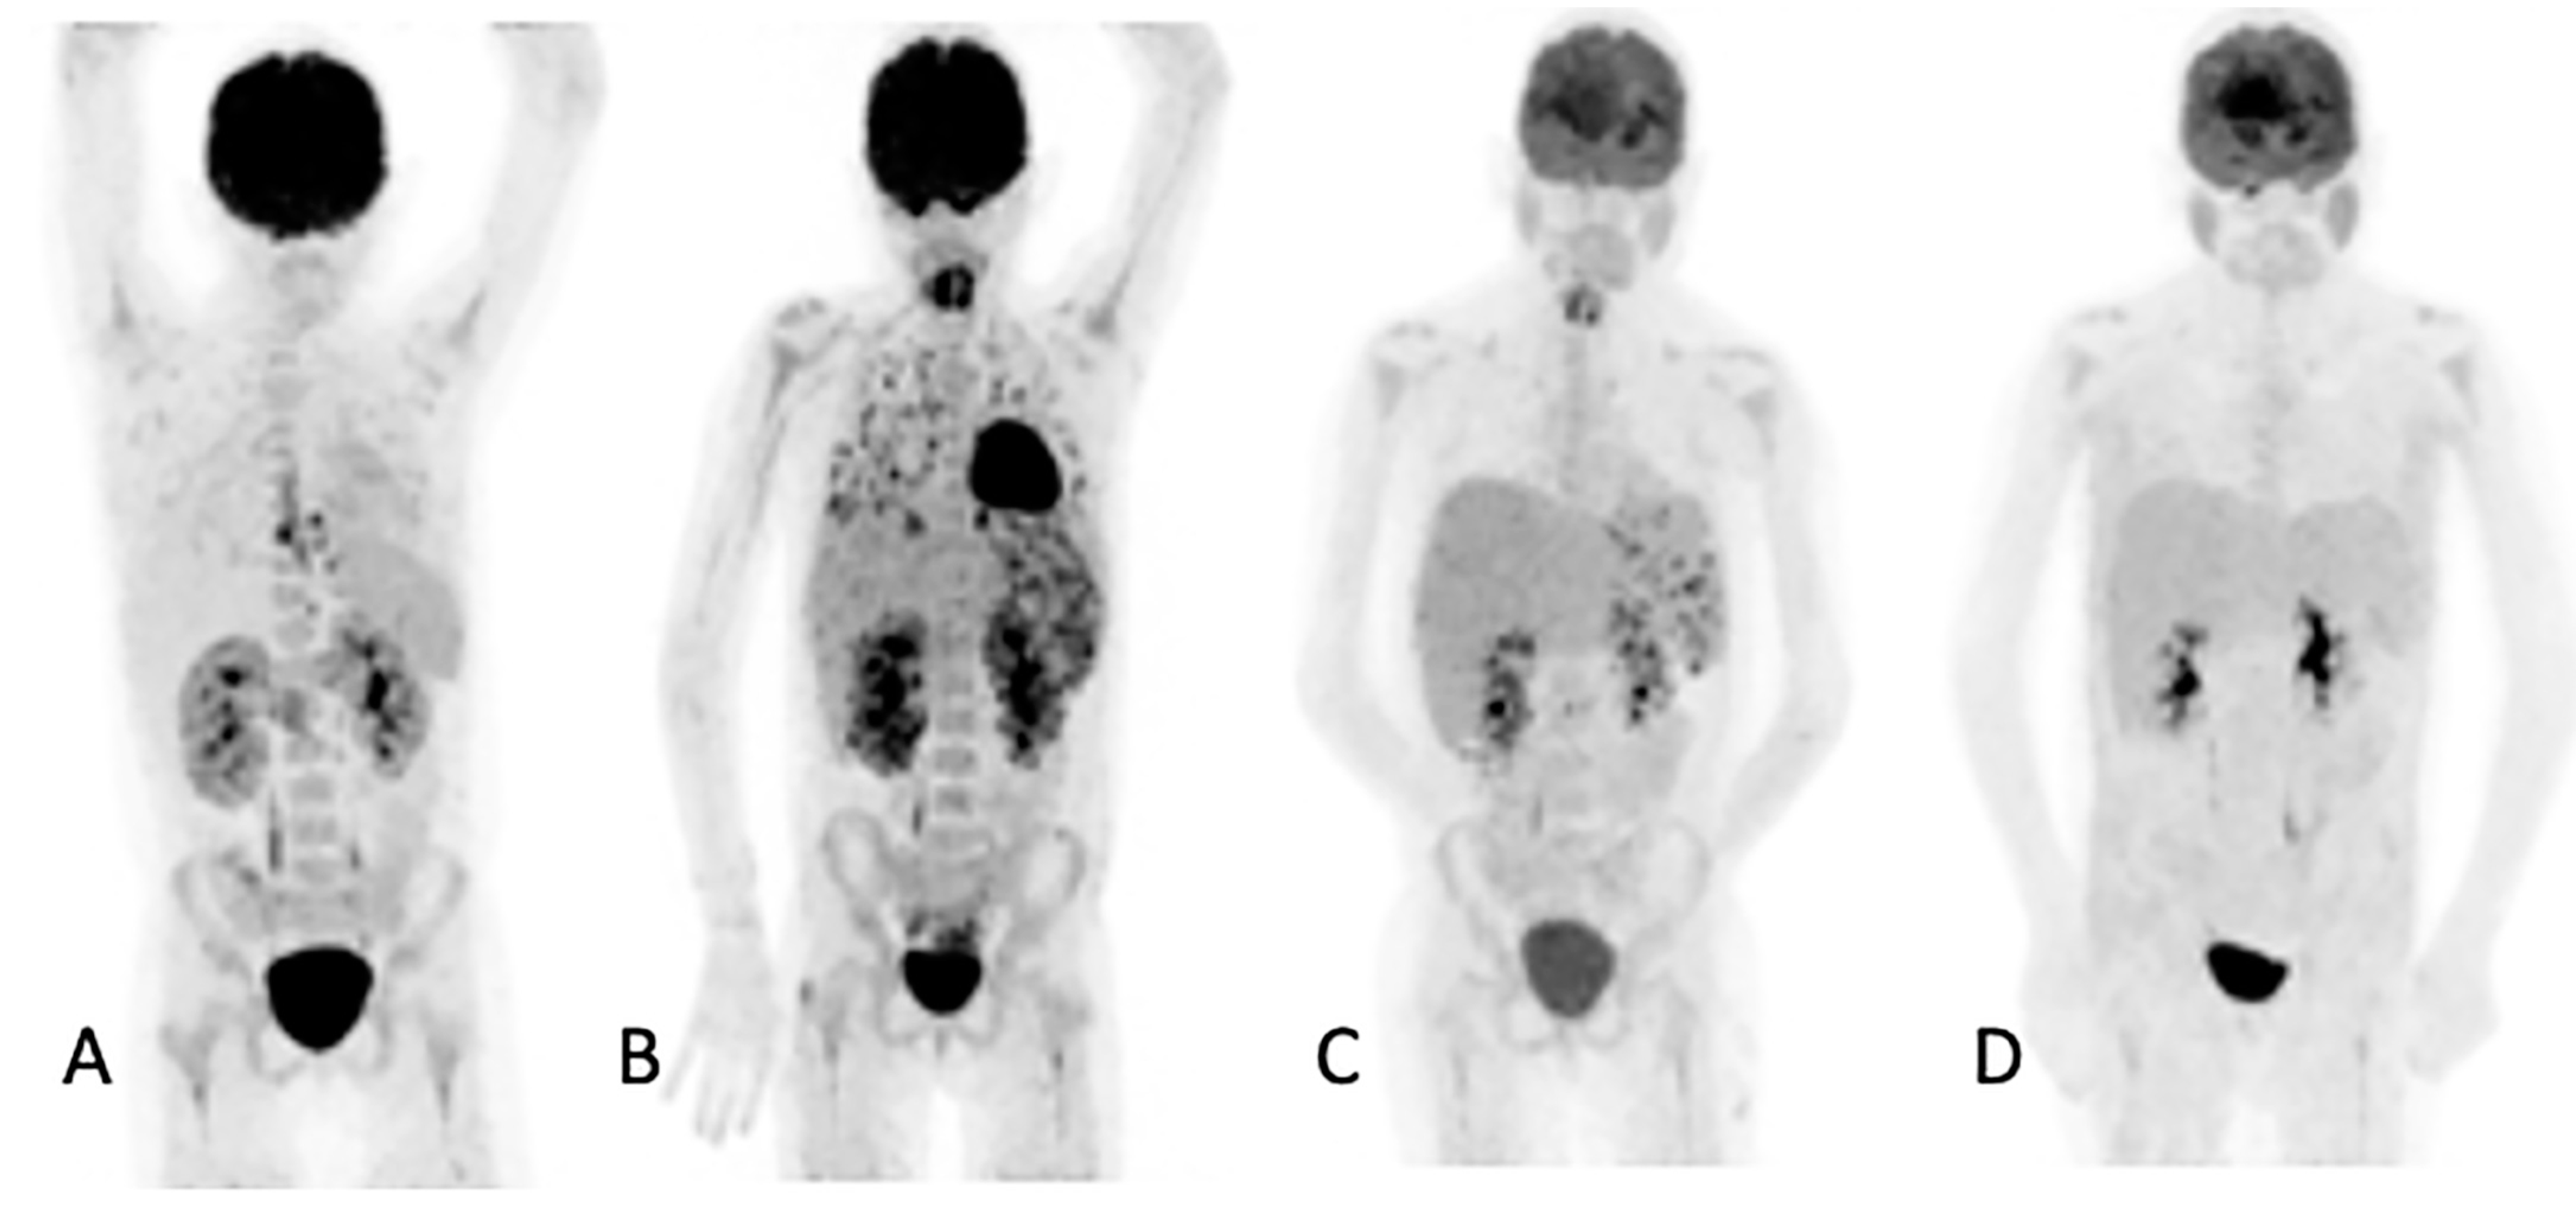

Figure 3.

Ten-year-old female with acute myeloid lymphoma who developed a fever, on chemotherapy, with no response to antibiotics. An abdominal ultrasound demonstrated bilaterally enlarged kidneys. Initial [18F]FDG PET/CT MIP image (A) showed focal metabolic uptake in kidneys, spleen and esophagus. She was started on antifungal treatment, but the fever persisted, and a repeat study (B) showed the worsening of renal splenic lesions with no pulmonary lesions. The antifungal treatment was changed; the fever subsided, and the serum infective markers decreased. A repeat [18F]FDG PET/CT performed after 6 weeks (C) showed resolution of the pulmonary and most of the renal and splenic lesions. The treatment was continued for another month, and a follow-up [18F]FDG PET/CT (D) showed a complete metabolic response that helped the clinician to end the antifungal treatment.